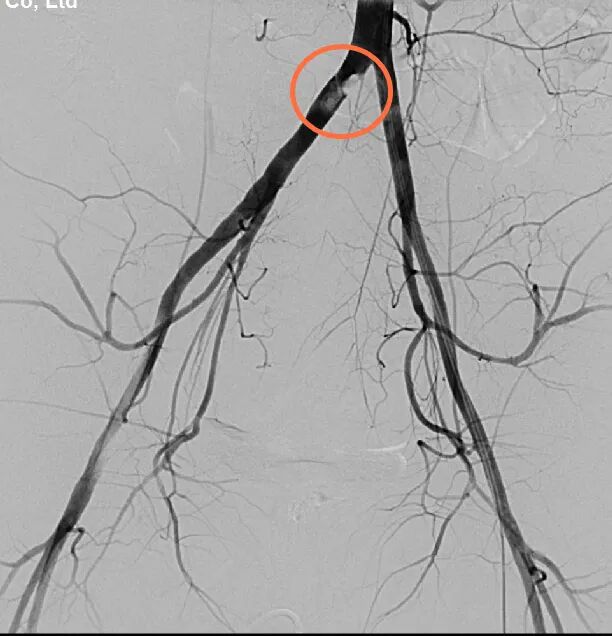

先行介入右侧髂动脉支架内隔绝术

来到市二院后,经过初步检查,吕先生被碾严重,肋骨骨折,腹壁肌肉断裂,肠管破裂,以及髋部、右臀部皮肤破裂受伤出血。CT检查中,还发现一个非常棘手的问题,右侧髂动脉与腹主动脉交界处有血肿,一旦破裂,就会有生命危险时间就是生命,普外一病区刘利亭主任当机立断,立即带领团队医护人员进入导管室,为吕先生实施侧髂动脉支架内隔绝术。在医护人员的不懈努力下,手术顺利完成。虽然拆掉了血肿这个最危险的“雷”,但吕先生的情况依然不容乐观。